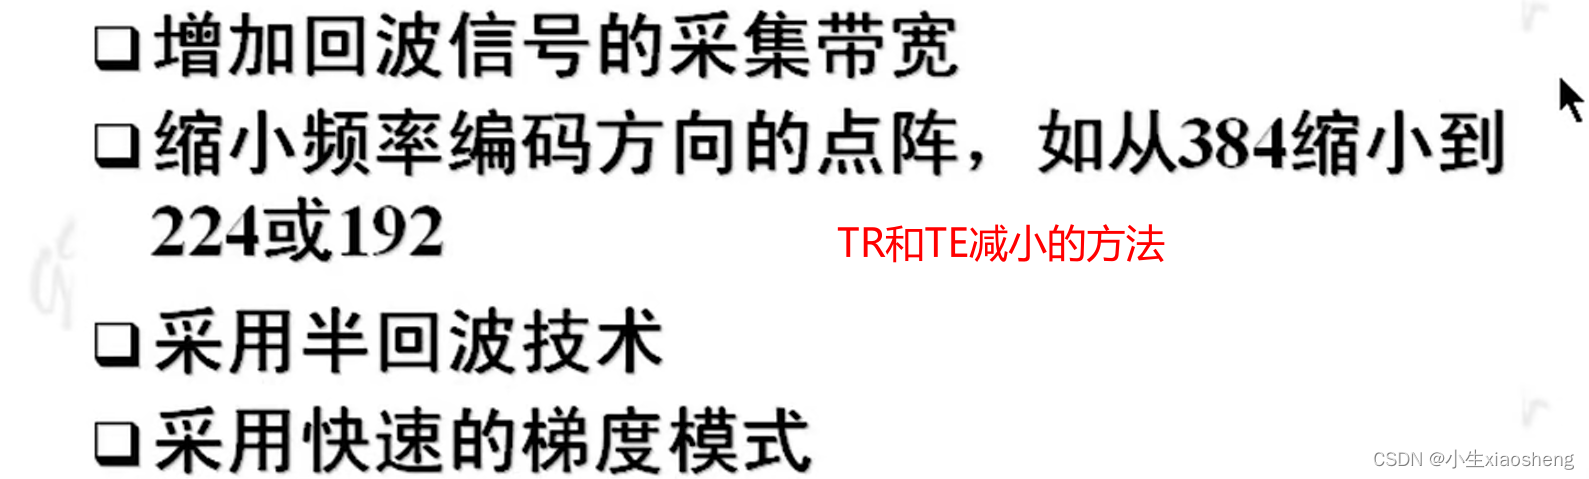

TR和TE要小一点能得到更好的效果图片。